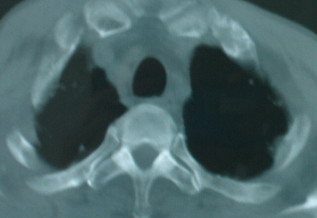

以下是引用卜一在2008-6-3 19:33:00的发言:[br]双肺结节,以双上肺分布为多,期间搀杂片状致密影及索条致密影。考虑:继发性肺结核伴血型播散可能性大。不除外肺泡ca的可能!另:椎体退变!

以下是引用panyishengct在2008-6-3 21:09:00的发言:[br]双上肺弥漫性小结节影,纵隔窗内钙化淋巴结影,考虑矽肺或/和tb可能性较大,不除外肺ca可能。腰椎考虑退变。 [br][br]